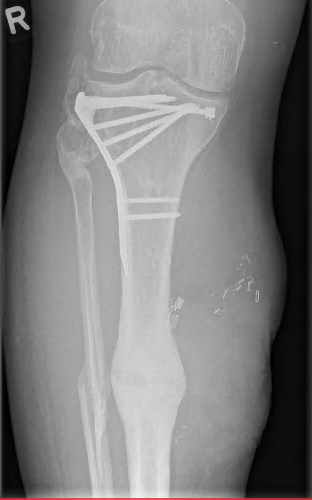

The patient underwent early physiotherapy for remobilization. Customized compression garments were worn for 6 weeks for flap remodeling. He was discharged to outpatient care on the 63rd day in a healthy condition with good scarring. The initial care was performed by the outpatient unit with weekly follow-up visits and short-term visits after 2 and 8 weeks (Figure 4 [Fig. 4] and Figure 5 [Fig. 5]), 6 months (Figure 6 [Fig. 6] and Figure 7 [Fig. 7]) and 1.5 years post-surgery (Figure 8 [Fig. 8] and Figure 9 [Fig. 9]). Given full weight bearing, the patient did not complain of any disturbance. A contrast CT performed at week 16 post discharge confirmed the efficacy of the AV loop (Attachment 1 [Att. 1]). Figure 5 [Fig. 5], Figure 6 [Fig. 6], Figure 7 [Fig. 7] and Figure 8 [Fig. 8] show the patient standing and able to walk with no crutches. The X-rays (Figure 10 [Fig. 10]) one year after bone fixation showed no sign of bone infection or pseudarthrosis after removal of the external fixator. No further surgical procedures were performed due to good overall patient satisfaction and adequate aesthetic outcome.

Figure 10: Posteropative X-rays after 1 year